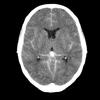

Identify the pathology

Left middle cerebral artery infarct